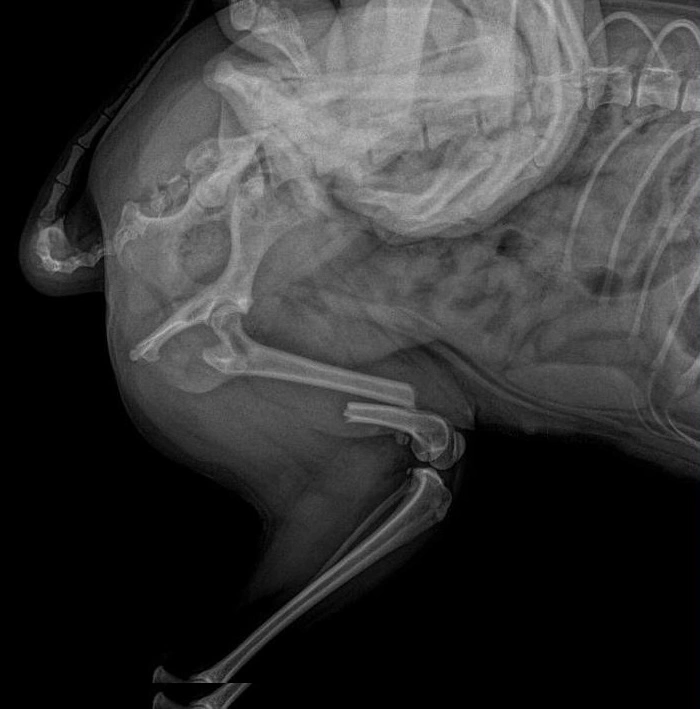

Теплі моменти з нашими пацієнтами

Ми піклуємося про кожного хвостика, як про власного. 🐾

Погляньте на наших щасливих відвідувачів.